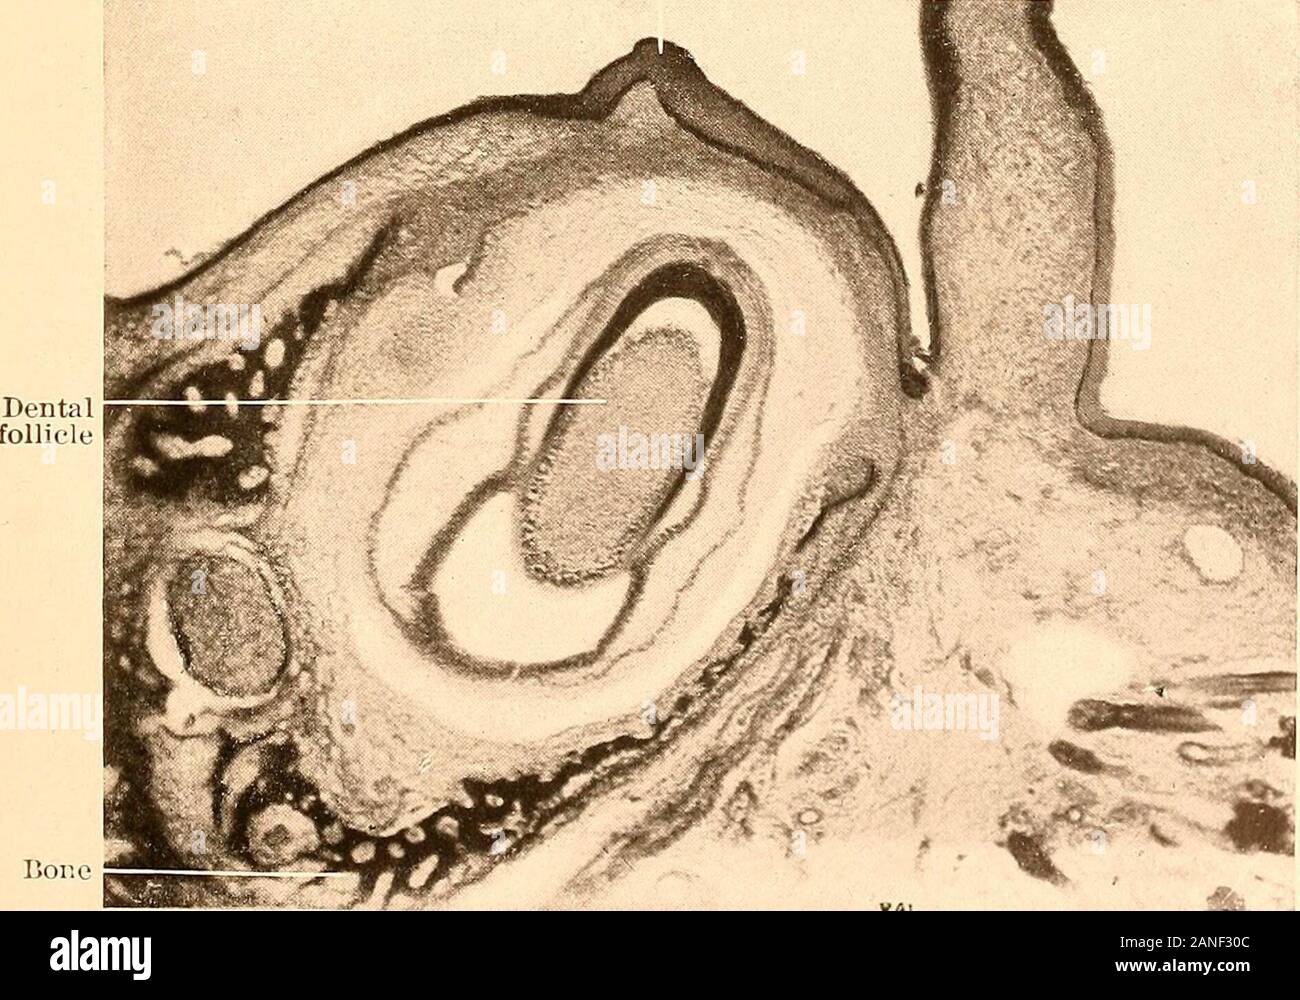

Oral mucous membrane pictorial representation

Principles and practice of operative dentistry . Mucous membrane What Is Dental Mucous Membrane The term mucous membrane is used to describe the moist lining of the gastrointestinal tract, nasal passages, and other body. The mucous membrane lining the inside of the mouth. Oral mucosa almost continuously lines the oral cavity. The oral mucosa is a mucous membrane, which lines the oral cavity and merges into the surface epidermis on the lips and into.. What Is Dental Mucous Membrane.